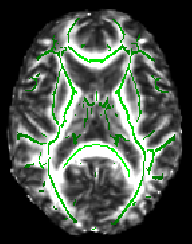

The script finishes by telling you to check whether a suitable threshold for the mean FA skeleton is 0.2 (a typical value used by the next script). For example, load the 4D FA data and the skeleton into FSLView:

cd stats fslview all_FA -b 0,0.8 mean_FA_skeleton -b 0.2,0.8 -l Green

The -b option sets sensible display range options, and in the case of the skeleton image, also controls the thresholding applied. Now turn on the movie loop; you will see the mean FA skeleton on top of each different subject's aligned FA image. If all the processing so far has worked ok the skeleton should look like the examples shown here (see the TBSS paper for more examples of different subjects' results underneath the skeleton). If the registration has worked well you should see that in general each subject's major tracts are reasonably well aligned to the relevant parts of the skeleton. If you set the skeleton threshold (in FSLView, the lower of the display range settings) much lower than 0.2, it will extend away towards extremes where there is too much cross-subject variability and where the nonlinear registration has not been able to attain good alignments. Remember the skeleton threshold for the next stage.